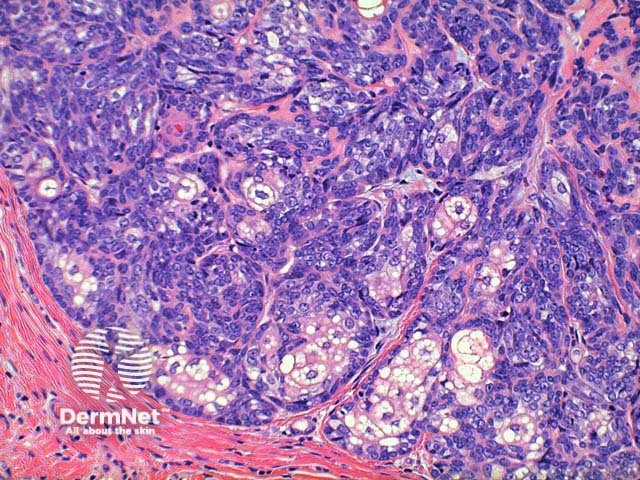

Scanning power of the histology of sebaceoma demonstrates a relatively well-circumscribed tumour nodule typically within the deep dermis frequently with attachment to the epidermis. Low power identifies a lobulated tumour, which may demonstrate areas of cyst formation (Figure 1). The tumour is comprised of basaloid cells and a minority of sebaceous cells in addition to small ducts with the crenelated eosinophilic lining seen in sebaceous ducts (Figures 2, 3 and 4). A variable number and distribution of sebocytes is seen, but should remain the minor proportion compared to the basaloid component. Frequent mitoses can be seen in this tumour, though cytological atypia is lacking (Figure 5).

Figure 4